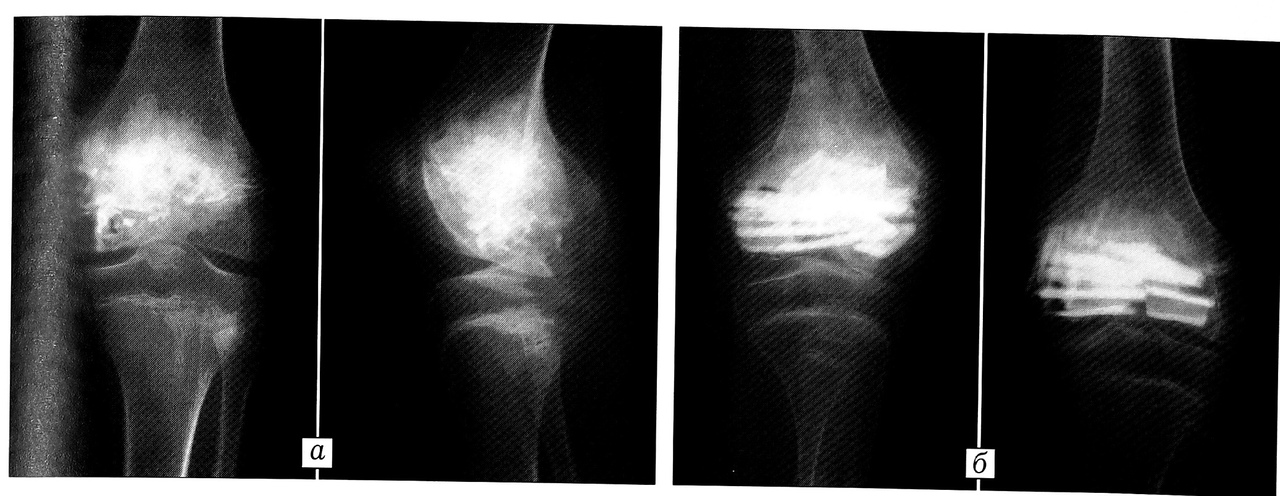

Рис. 6. Больная М. 11 лет. Хондробластома проксимального эпифиза левой бедренной кости. а — рентгенограмма, б — компьютерная томограмма до операции: дифференциальная диагностика с дистрофическими кистами головки бедра. Остеолитическая деструкция проксимального эпифиза левой бедренной кости, отграниченная зоной склероза. Произведена прицельная биопсия под контролем КТ с контрастированием. Контрастное вещество распространилось вокруг очага, что свидетельствует о наличии в нем ткани; в — компьютерная томограмма после операции (субхондральная околосуставная резекция головки бедра, пластика дефекта перфорированными поверхностно-деминерализованными аллотрансплантатами).

При разрушении суставного хряща и выходе опухолевых масс в полость сустава объем операции значительно увеличивался. В таких случаях доступ к опухоли осуществляли путем резекции пораженного суставного хряща эпифиза, что при локализации очага в головке бедра требовало ее вывихивания. После выполнения внутрисуставной краевой резекции (20 операций) дефект кости замещали кортикальными аллотрансплантатами, а дефект суставного хряща — фигурными губчатыми аллотрансплантатами с хрящевым покрытием (рис. 7).

Рис. 7. Больная Т. 11 лет. Хондробластома дистального метаэпифиза левой бедренной кости. a — рентгенограммы до операции; б — после операции (внутрисуставная краевая резекция дистального метаэпифиза бедра, замещение дефекта кортикальными аллотрансплантатами в сочетании с губчатыми аллотрансплантатами, покрытыми хрящом).